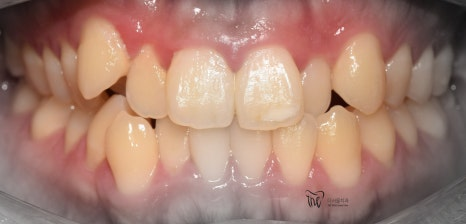

부정교합 2급 이라는 것은, 하악보다 상악이 더 전방에 위치되거나 또는 상악의 치아들이, 하악 치아들보다 더 앞쪽에 위치되어 있는것을 뜻하며

증세를 갖고 계셨던 분의 임상 증례를 보여드립니다. 교정 치료를 통해서 2급 부정교합이 개선 되었으며 치료를 끝으로, 턱 끝에 보형물